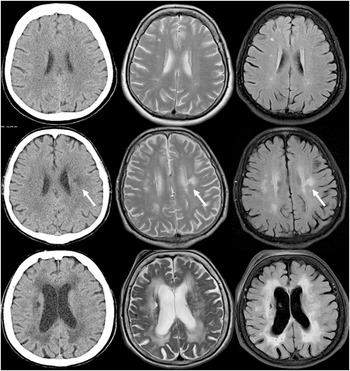

Conventional brain imaging of white matter lesions (Chapter 11) - Cerebral Small Vessel Disease

Conventional brain imaging of white matter lesions (Chapter 11) - Cerebral Small Vessel Disease

Conventional brain imaging of white matter lesions (Chapter 11) - Cerebral Small Vessel Disease,

Conventional brain imaging of white matter lesions (Chapter 11) - Cerebral Small Vessel Disease, Nonrigid Stabilization of the Spine - Problems Observed: Screw Loosening/Breakage/Implant Failure/Adjacent Segment Degeneration | SpringerLink,